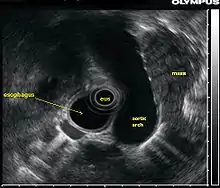

La ecografía endoscópica o ecoendoscopia es un procedimiento en el que se combina la técnica de endoscopia con el uso de ultrasonidos, obteniendo de esta forma imágenes de gran calidad de los órganos internos, sobre todo del esófago, estómago, páncreas y mediastino.[1] Si se combina esta técnica con la ecografía Doppler, los vasos sanguíneos cercanos a estas estructuras también pueden ser evaluados.

Para la realización de la ecografía endoscópica del tracto digestivo superior, se inserta una sonda en el esófago que luego pasa por el estómago y luego por el duodeno durante un procedimiento llamado esofagogastroduodenoscopia. Este procedimiento se realiza para la detección del cáncer de páncreas, cáncer de esófago y cáncer gástrico, así como tumores benignos del tracto gastrointestinal superior. Por otro lado, mediante la inserción de una aguja a través del revestimiento de los órganos a estudiar, permite la caracterización de la biopsia que se realizó en el tracto gastrointestinal superior.

Es importante resaltar que la ecografía endoscópica se realiza con el paciente sedado. El endoscopio se introduce por la boca y avanza a través del esófago hacia el área que se desea estudiar. A medida que el endoscopio es insertado a través del tracto digestivo, se pueden observar órganos adyacentes al tracto gastrointestinal (hígado, páncreas, glándulas suprarrenales), para ver si son anormales, en caso de que se sospeche un cáncer, se puede hacer una biopsia por un proceso llamado aspiración con aguja fina.

La ecografía endoscópica también puede ser utilizada para visualizar los ganglios linfáticos presentes en la cavidad torácica que rodean las vías respiratorias (bronquios), mediante la introducción de una sonda de ultrasonido endoscópico al esófago; esta técnica es muy útil para el diagnóstico de cáncer de pulmón. Otro método para realizar el ultrasonido de las vías respiratorias es, introducir la sonda endoscópica dentro de los propios bronquios, esta técnica es conocida como ecografía endobronquial.

La calidad de la imagen producida es directamente proporcional a la frecuencia utilizada, por esta razón a medida que la frecuencia aumenta se produce una mejor imagen. Sin embargo, el ultrasonido de alta frecuencia no es tan fácil introducirlo al cuerpo humano, así como el ultrasonido de baja frecuencia. Sin embargo, el equipo de baja frecuencia no da una imagen clara de los órganos haciendo el examen más difícil.